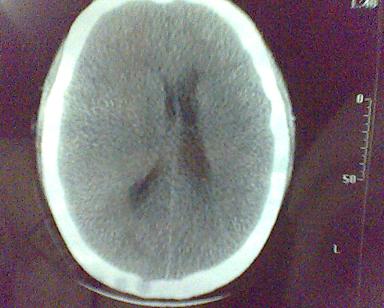

男 31岁 短暂性四肢抽搐 呼叫不应  头胀痛4个多月 无发热 4年前遭棒击头部,当时未到医院检查。余无特殊。病人特穷,未作增强。

这是一个边缘清晰的等密度的囊性占位.密度比较均匀,周围无水肿,我顷向于脑脓肿的可能性大.

图象质量太差啦,拜托照好一点,好象从临床症状不太支持脓肿,脑实质内没有水肿,只有轻度战位效应。脓肿壁应再厚点。囊性占位比较合适,建议强化。